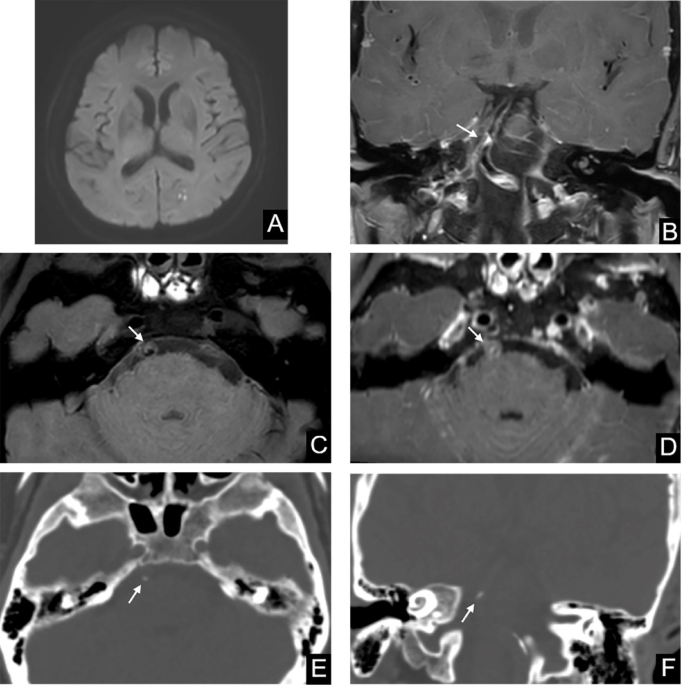

Representative case of AAE (+) stroke in a 61-year-old male patient. DWI (A) demonstrated multiple scattered infarcts seen at the left occipital lobe (arrowhead, restricted diffusion). Post-contrast vessel wall MRI acquired in the coronal plane (B) demonstrated the most significant stenosis with wall thickening at the proximal basilar artery. Pre-contrast (C) and post-contrast (D) vessel wall MRI images show an eccentric plaque at the corresponding site in the axial images(arrow). Axial (E) and coronal (F) CT images reveal the presence of spotty and intimal predominant calcification (arrow) in the corresponding image slices.